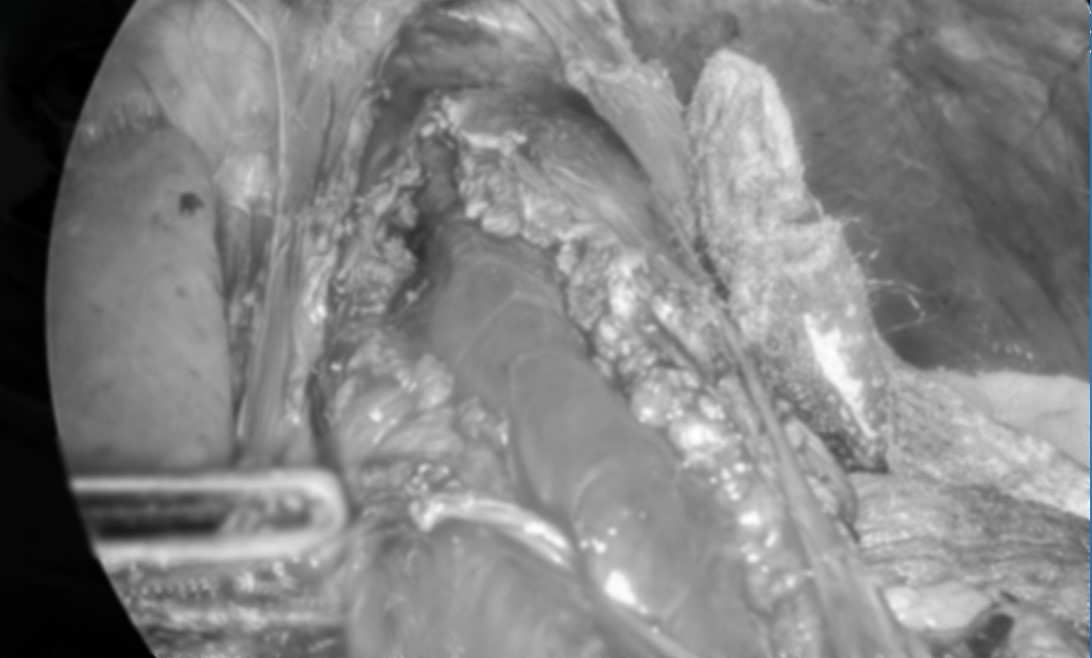

Cuộc phẫu thuật kéo dài gần 2 giờ đã được thực hiện thành công với kỹ thuật cắt dọc lớp cơ ở vùng tâm vị và một phần thực quản, đồng thời tạo van bán vòng trước bằng đáy vị để ngăn ngừa biến chứng trào ngược sau mổ.

Tạo hình thực quản - Ảnh BVCC